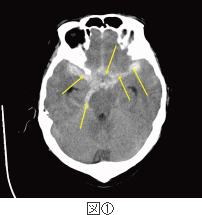

くも膜下出血の急性期看護。

くも膜下出血の原因メディカルノート。

くも膜下出血とは東京銀座の脳梗塞・脊髄損傷クリニック。

くも膜下出血とは北青山Dクリニック キレーション療法部門。

くも膜下出血の症状・5つの前兆をチェック健診会東京メディカルクリニック,夜間診察も。

くも膜下出血についてくも膜下出血の症状と治療法 横浜新都市脳神経外科病院。

脳卒中 くも膜下出血 の原因究明をめざして - 研究へのご協力のお願い。

くも膜下出血の前兆・原因・症状 漫画でわかる 横浜もえぎ野クリニック 脳神経外科・脳神経内科横浜市・青葉区・青葉台。

危険な病気 くも膜下出血の治療・予防病気と治療の検索サイト「メディカルブレイン」。

三種類の予防対策を日常に取り入れてくも膜下出血を防ぐ 脳梗塞・脊髄損傷後遺症の幹細胞治療ニューロテックメディカル。

くも膜下出血 - とくなが内科胃腸科外科クリニック熊本市 東区 内視鏡胃カメラ 大腸カメラかかりつけ医。

くも膜下出血の死亡率について再生医療脳梗塞・脊髄損傷の幹細胞治療ニューロテックメディカル。

くも膜下出血について - 脳梗塞・脊髄損傷クリニック。

くも膜下出血とは症状、検査、治療について千葉西総合病院。